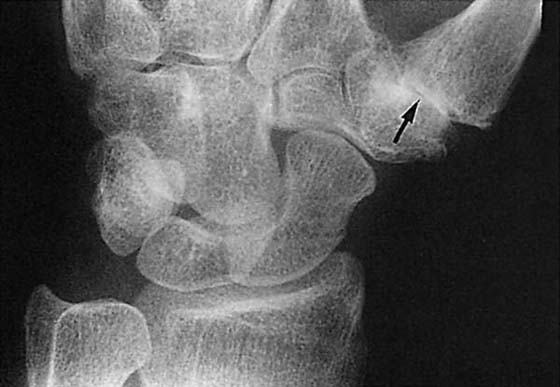

Figure 13-4 This posteroanterior view of the wrist shows a fracture of the proximal third of the scaphoid (arrow) with an associated cyst.

images